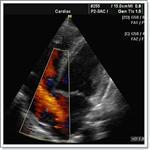

- Эхокардиография – создает трехмерное изображение органа, определяет скорость и характер движения крови.

- Ультразвуковое исследование магистральных сосудов и кардиальных структур. Данная техника позволяет визуализировать отклонения в нормальном строении клапанов и перегородок. Информативно УЗИ также и для подтверждения наличия регургитации.

- УЗИ с допплерографией – наиболее ценный метод, он позволяет оценить функционирование клапанов, затруднение выброса крови или ее обратное движение после сокращения, состояние крупных сосудов, размеры полостей сердца и толщину миокарда, гемодинамические показатели;